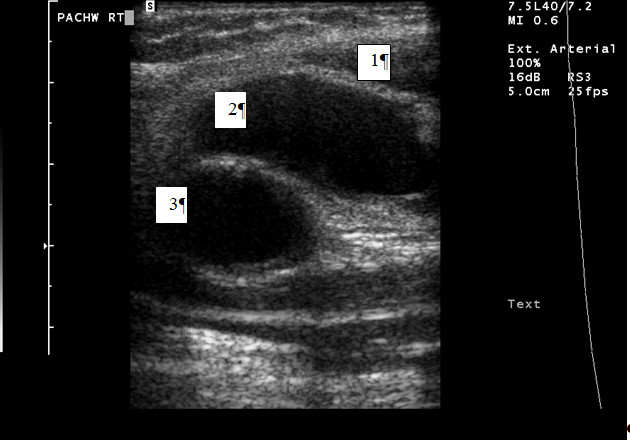

U pacjenta występowały objawy chromania przestankowego obu kończyn dolnych i pośladków. W badaniu przedmiotowym stwierdzano osłabienie tętna w pachwinach oraz wyraźnie słyszalny szmer naczyniowy. Wykonano nakłucie tętnicy udowej prawej w celu wykonania angioplastyki tętnic biodrowych. Następnego dnia w nakłutej pachwinie stwierdzono obecność krwiaka a osłuchowo obecność szmeru naczyniowego. Wykonano badanie dupleksowe uzyskując poniższy obraz. Sytuacja przedstawiona na rycinie odpowiada: